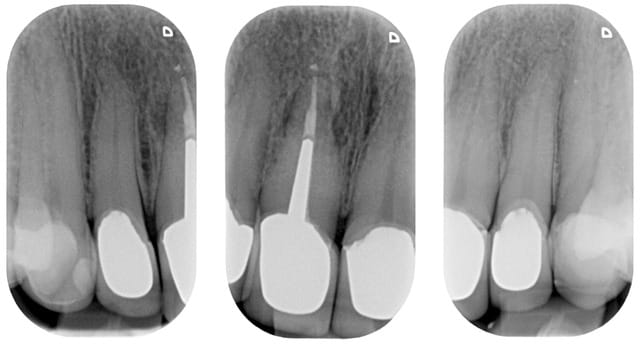

Oui, voici les radios

Pour la 4 (22) au tout début j'avais fait une ccc, mais le collet malgré une chape opaque était grisé, on a donc refait une ccm!